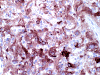

The mass consists of a mixture of spindle cells and clear cells. There is a rich vascular network (Panel A) with sinsusoidal dilatation but no anastomosis of the vascular channels. The endothelial cells appear lean and not protruding into the vascular channel. The clear cells appear to have foamy cytoplasm (̃ in Panel B). The nuclei are hyperchromatic and may appear slighly grooved or lobuated. On immunohistochemistry, the foamy cells are strongly reactive for inhibin (Panel C). These cells are also reactive for S100 protein (Panel D)  and neural specific enolase (Panel E) . No immunoreactivity for epithelial membrane antigen (EMA) is observed (Panel F). The tumor is not immunoreactive for cytokeratin.

Microscopically, hemangioblastomas consist of foamy to clear stromal cells interspersed with endothelium lined vascular channels.  Clear vacuoles within the stromal cells can be stained with Oil red-O or similar stain if applied to frozen sections.  The stromal cells stain strongly for epidermal growth factor receptor (EGFR) and platelet-derived growth receptor factor alpha (PDGF-alpha) 12 and inhibin 13. The stromal cells are typically negative for epithelial membrane antigen (EMA) and cytokeratin 14.  In a small number of cases, the stromal cells express glial fibrillary acidic protein (GFAP)  7, 14 and S100 protein 14. These staining results should be interpreted with case as they may represent entrapped glial cells. The admixed capillaries will stain for with typical endothelial markers (Factor-VIII and others) 15, but the stromal cells are typically negative for the endothelial markers. To this date, the pathogenesis and cell origin of hemangioblastomas is not certain.